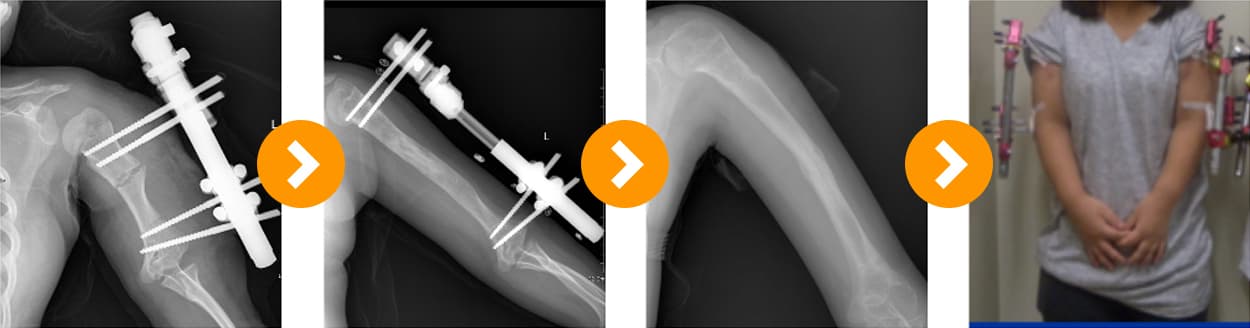

Achondroplasia: Upper Limb Lengthening 10 cm